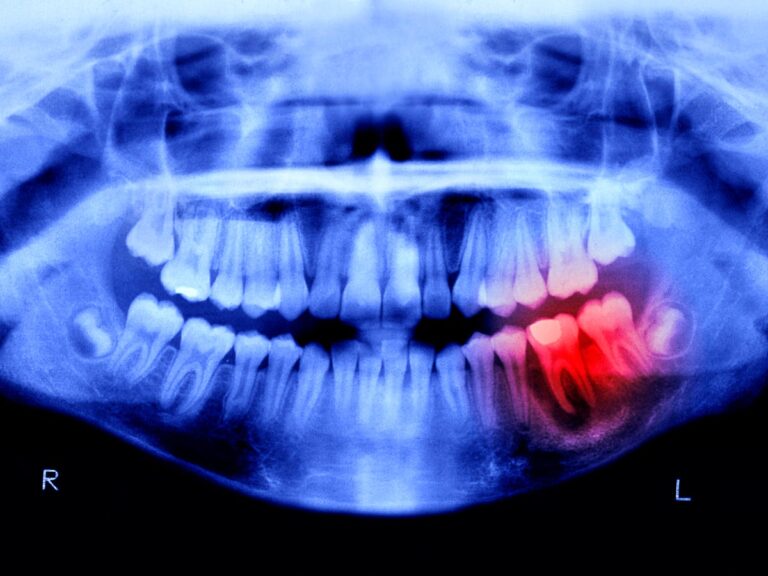

این مطلب اولین بار در سایت گیمفا گیمفا: اخبار، نقد و بررسی بازی، سینما، فیلم و سریال در لینک انسان‌ها تا ۴ سال آینده می‌توانند دندان‌های جدید رشد دهند نوشته شده است.در حالی که استخوان‌های ما قادر به بازسازی پس از شکستگی هستند، دندان‌ها این شانس را ندارند و همین امر باعث می‌شود میلیون‌ها نفر در سراسر جهان با نوعی از بی‌دندانی مواجه باشند. اکنون محققان ژاپنی داروی امیدوارکننده‌ای برای رشد مجدد دندان‌ها تست کرده‌اند. انسان‌ها تا ۴ سال آینده می‌توانند دندان‌های جدید رشد دهند The post انسان‌ها تا ۴ سال آینده می‌توانند دندان‌های جدید رشد دهند first appeared on گیمفا: اخبار، نقد و بررسی بازی، سینما، فیلم و سریال.